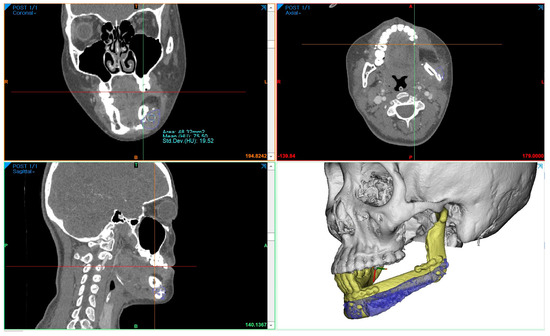

Three years after cancer surgery, 2-stage dental implant (TS-III CA; Osstem Implant Co., Busan, Republic of Korea) installation was performed outpatiently under local anesthesia, the final implant prosthesis was completed 4 years after surgery, and the patient recovered functionally and aesthetically (Figure 8).

Figure 8. In total, 40 months after cancer surgery, the secondary implant surgery was performed, and the surrounding mucosa was sutured to the periosteum of the fibula to form an attached gingiva: (A) preoperative intraoral photo with hairy fibular skin; (B) postoperative intraoral photo; (C) removed fibular skin; (D) stich-out after 2 weeks; (E) panoramic view immediately after dental implant 1st surgery; (F,G) temporary prosthesis after 4 months; (HJ) Recovery of masticatory function was completed without inflammation after delivery of the final prosthesis 4 years after cancer surgery.